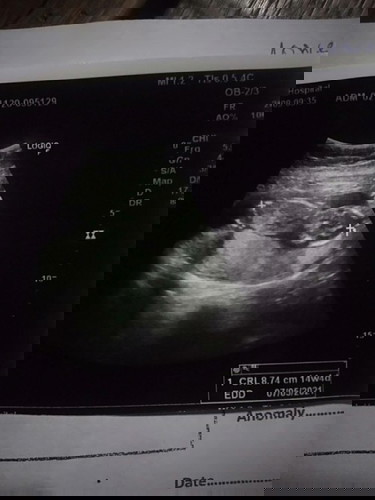

วันนี้ไปหาหมอมาค่ะหมอบอกน้องตัวเล็ก 14+5 w #ขอบคุณค่ะ

หอมบอกน้องตัวเล็ก 14+5 วีค แม่คิดว่ายังไงค่ะ #ขอบคุณค่ะ